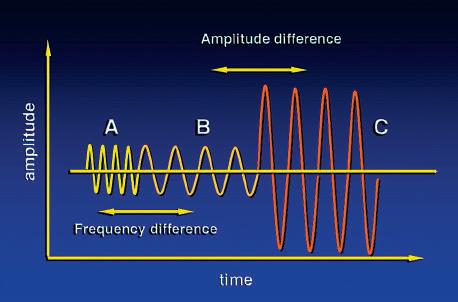

Conventional B-mode ultrasound imaging uses pulse-echo transmission, detection, and display techniques. Brief pulses of ultrasound energy emitted by the transducer are reflected from acoustic interfaces within the body. Precise timing allows determination of the depth from which the echo originates. When pulsed wave ultrasound is reflected from an interface, the backscattered (reflected) signal contains amplitude, phase, and frequency information (Fig. 1.32). This information permits inference of the position, nature, and motion of the interface reflecting the pulse. B-mode ultrasound imaging uses only the amplitude information in the backscattered signal to generate the image, with differences in the strength of reflectors displayed in the image in varying shades of gray. Rapidly moving targets, such as red cells in the bloodstream, produce echoes of low

FIG. 1.32 Backscattered Information. The backscattered ultrasound signal contains amplitude, phase, and frequency information. Signals B and C differ in amplitude but have the same frequency. Amplitude differences are used to generate B-mode images. Signals A and B differ in frequency but have similar amplitudes. Such frequency differences are the basis of Doppler ultrasound.